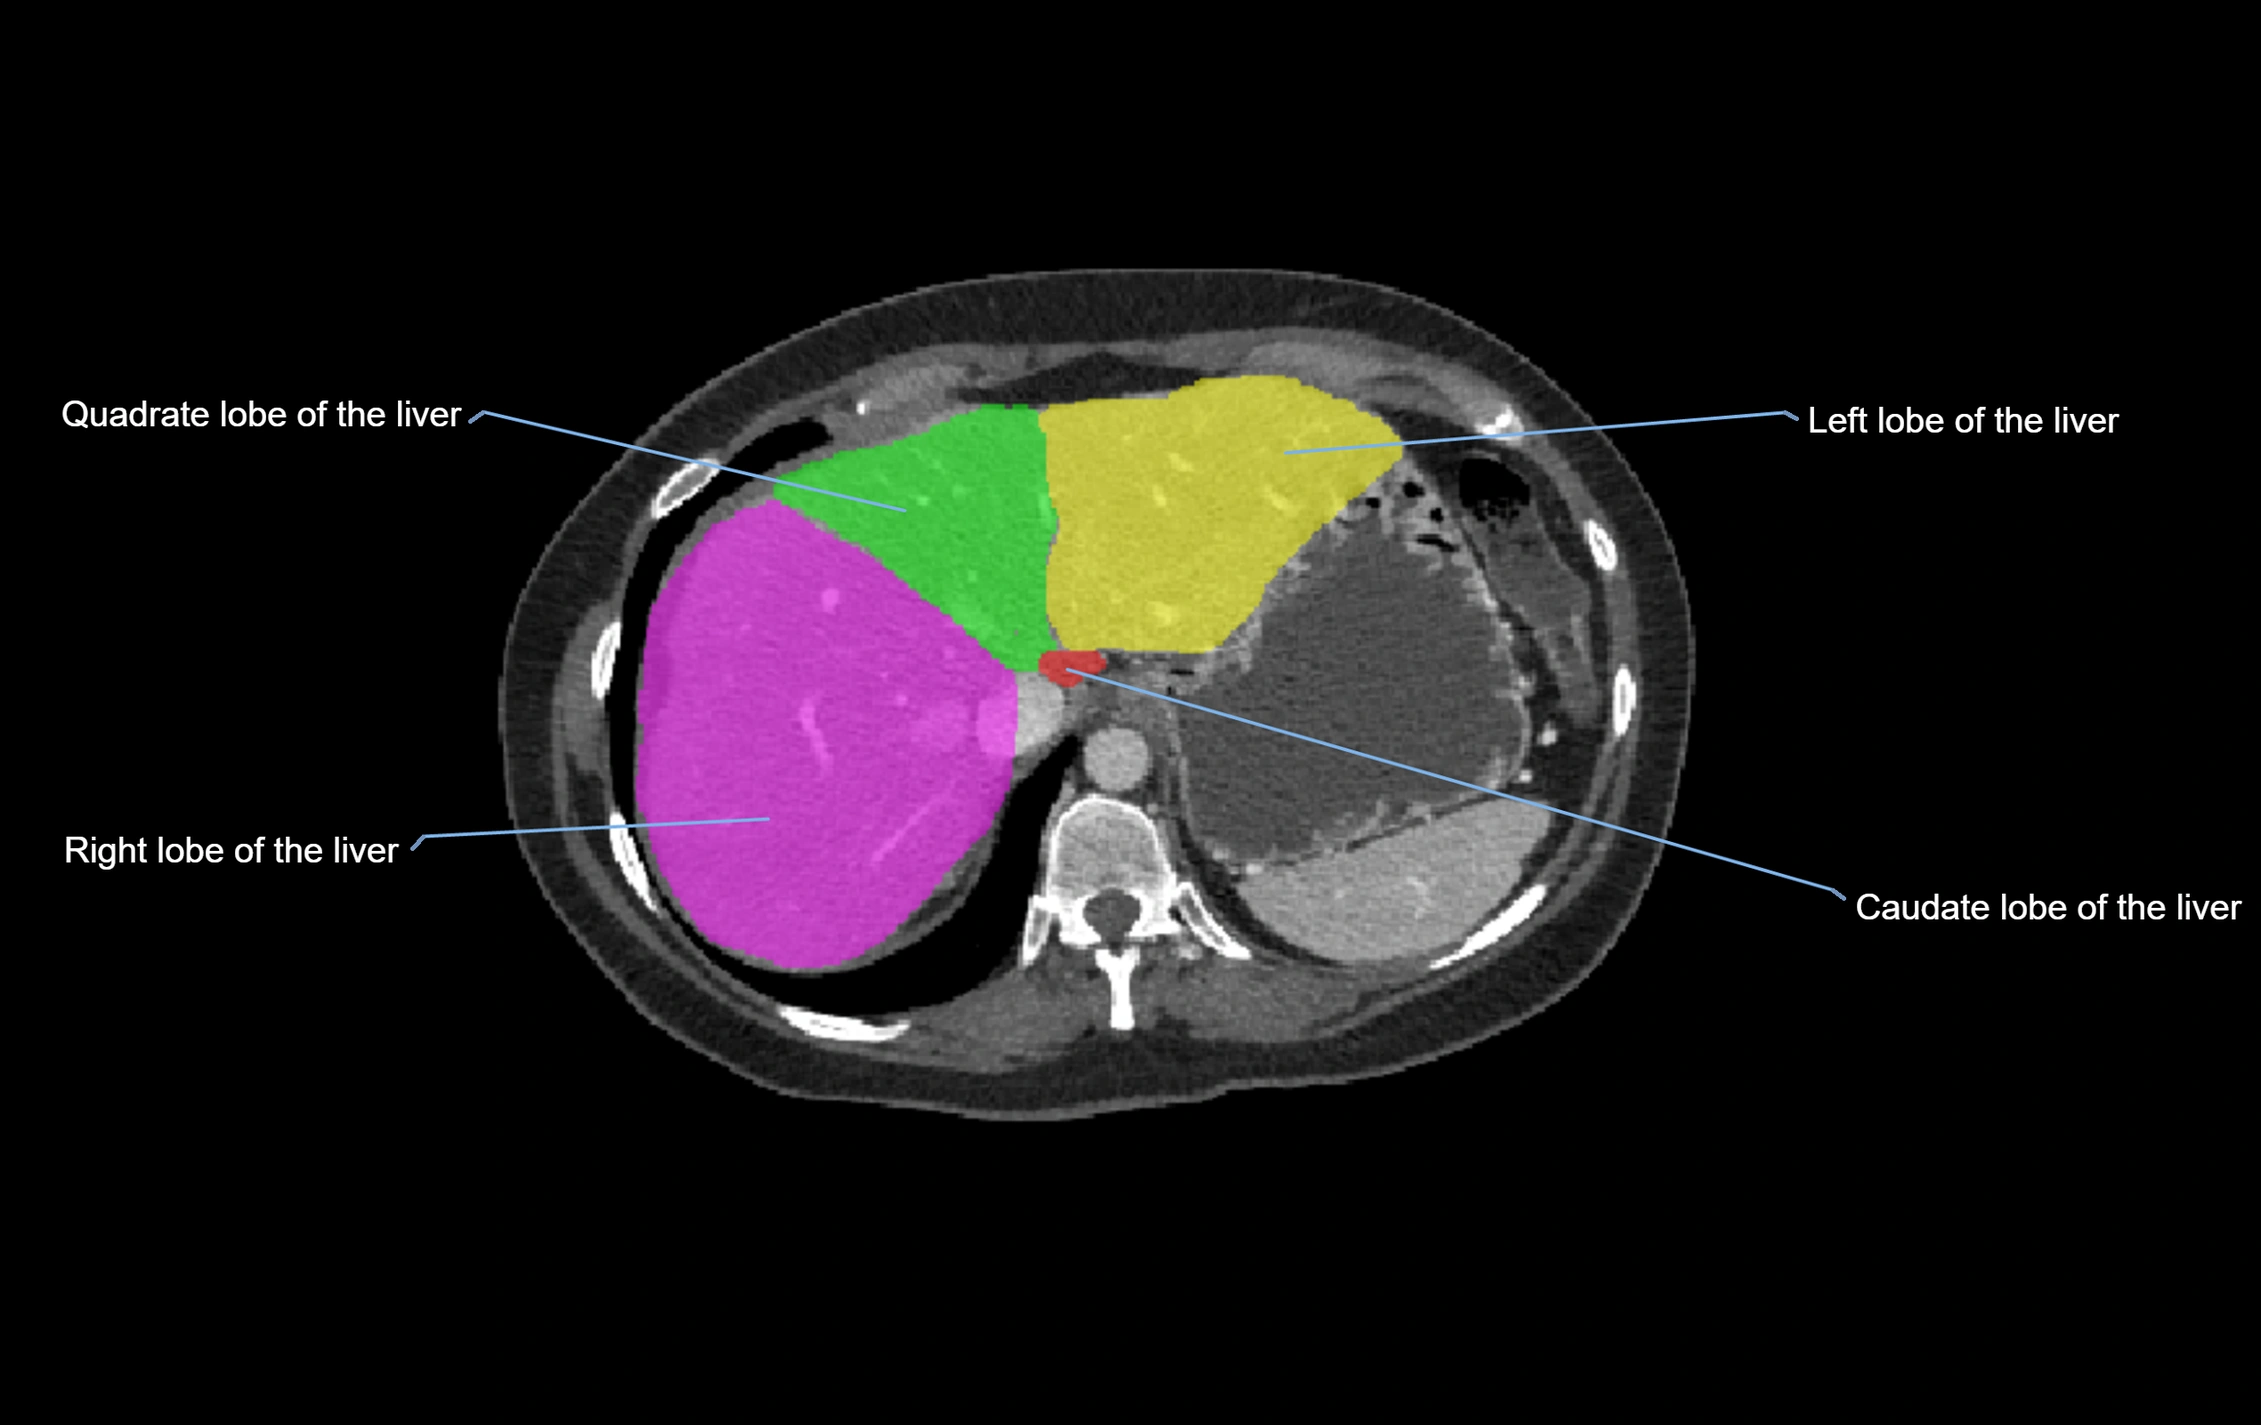

The caudate lobe of the liver is a distinct anatomical subdivision of the liver, designated as segment I in Couinaud’s classification. It lies on the posterior surface of the liver, between the fissure for the ligamentum venosum (left boundary) and the groove for the inferior vena cava (IVC) (right boundary). Superiorly, it is related to the posterior liver surface, and inferiorly it is separated from the left lobe by the porta hepatis.

CT Appearance

CT Pre-Contrast:

• Caudate lobe appears as a soft-tissue density, isodense to the rest of the liver

• Enlargement may be appreciated in cirrhosis or Budd–Chiari syndrome

CT Post-Contrast:

• Homogeneous enhancement in the portal venous phase, similar to rest of liver

• Independent venous drainage into the IVC may be visualized

• Lesions follow characteristic CT enhancement patterns (HCC: arterial hyperenhancement with washout; hemangiomas: peripheral nodular enhancement with centripetal fill-in)

CT Venous Phase (functional significance):

• Caudate lobe often enhances relatively more than other lobes in Budd–Chiari syndrome, due to preserved venous outflow

MRI image

image